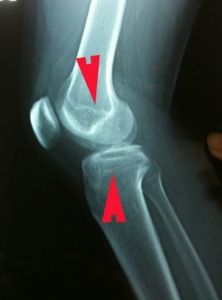

兒童的四肢長骨幹骺端與骨骺之間有一盤狀軟骨結構,稱為骺板。

骨骺是兒童出生後在不同的時間內出現的二次骨化中心.

骨骺和骺板都是未成熟的四肢長骨的生長區域,

也是兒童骨骼的最薄弱和最易骨折的部位。

骨骺線閉合,是骨骼發育的一個過程。骨骺與乾骺端之間的軟骨,在幼兒的x光片上表現為一條較寬的透光帶,它隨著年齡的增長而逐漸變短,當骨骺與乾骺端的軟骨完全骨化後,就形成一條緊密的縫,此時骨骺線完全閉合,骨骼停止生長。